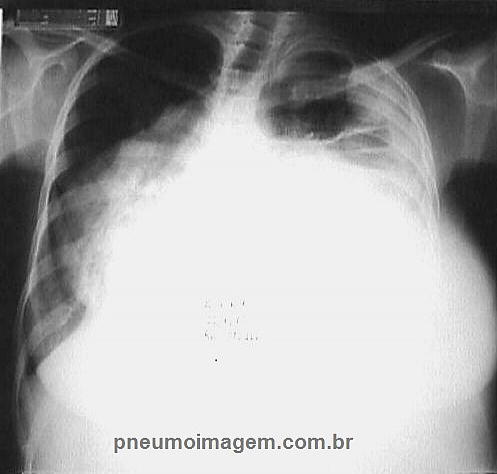

Os derrames pleurais malignos (DPM) são situações comuns tratadas tanto por pneumologistas como por cirurgiões torácicos. Nos últimos anos, vários ensaios clínicos randomizados foram publicados e mudaram o panorama da gestão do DPM. A European Respiratory Society (ERS) e a European Association for Cardio-Thoracic Surgery (EACTS) estabeleceram uma colaboração multidisciplinar de clínicos com experiência no manejo do DPM com o objetivo de produzir uma revisão abrangente da literatura científica.